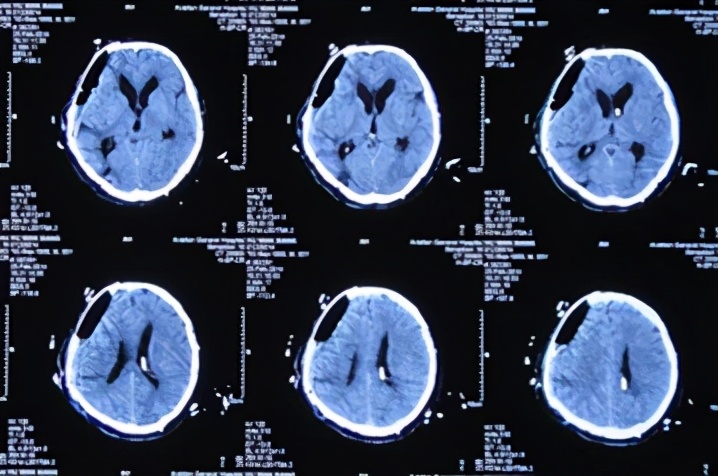

患者于2013年9月17日凌晨因车祸致头部外伤、昏迷,急诊于山东省聊城市某医院就诊,头CT检查发现双额及右颞叶多发脑挫裂伤并右侧脑室受压、中线左移(图-1),当天进行了右侧额颞叶脑挫裂伤血肿清除并去骨瓣减压术,术后头CT:去骨瓣减压术后状态(图-2)。

图-1:2013年9月17日术前头CT

图-2:2013年9月17日术后头CT